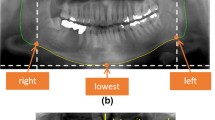

X-ray images are essential data sources for checking the condition of the teeth, gums, jaws, and bone structure of the mouth. Tooth recognition is fundamental in image-processing-based diagnoses. In most previous recognition studies, only four-axis-based object-detection models have been considered because they perform normal object detection while the object is resting on a flat surface. However, because the teeth have various orientations, the existing four-axis-based model leads to inaccurate and inefficient recognition results. Thus, in this study, we propose a five-axis-based object-detection model that considers the orientation of the tooth. Based on a tooth-image dataset labeled using the five-axis ground truth, our proposed method processed five-axis annotated data by employing a variant of the faster region-based convolutional neural network. In the experiment, our proposed method outperformed the existing four-axis approach, both qualitatively and quantitatively. The experimental results indicated that the proposed five-axis-based recognition model will be an important basis for a dental-image-based diagnosis.